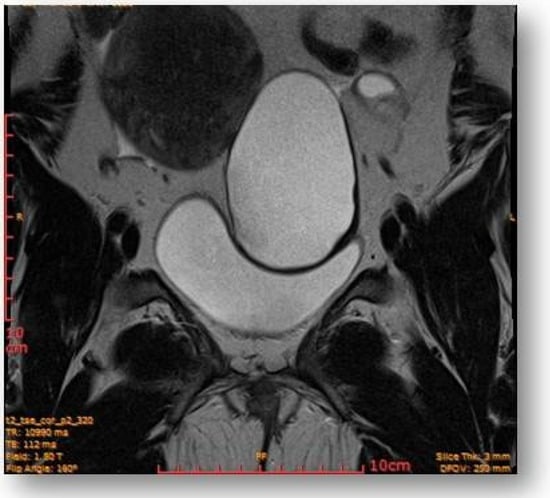

Left parauterine, between the left lateruterine wall and the left ovary, was attached to the anterior contour of the uterine round ligament, and an ovoid cystic lesion of approximately 100/68/50 mm (oblique CC/AP/LL) is evident (Figure 5).

Left parauterine, between the left lateruterine wall and the left ovary attached to the anterior outline of the round ligament, an ovoid cystic lesion of 100/68/50 mm is evident.

This showed probably proteinaceous fluid content and mildly irregular wall thickness up to ~4–5 mm (on the right lateral contour) and with a mural micronodule of ~5 mm with contrast uptake at the level of the left antero-lateral contour. The appearance advocated the first hypothesis for a “border-line” left paraovarian cyst, with suspicious elements of neoplastic transformation (Figure 6). It presented the following relationships: anteriorly, it imprints the anterior median-paramedian left pelvic wall, posteriorly with the uterine round ligament, urinary bladder, medially (to the right) with the uterus and urinary bladder, laterally (to the left) with the left ovary.

Ovoid cystic lesion imprints the urinary bladder without invasion into it.